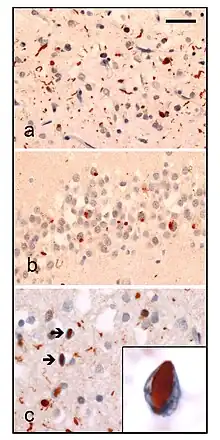

| Neuropathologic analysis of brain tissue from FTLD-TDP patients. Ubiquitin immunohistochemistry in cases of familial FTLD-TDP demonstrates staining of (a) neurites and neuronal cytoplasmic inclusions in the superficial cerebral neocortex, (b) neuronal cytoplasmic inclusions in hippocampal dentate granule cells, and (c) neuronal intranuclear inclusions in the cerebral neocortex (arrows). Scale bar; (a) and (b) 40 μm, (c) 25 μm, insert 6 μm. | |